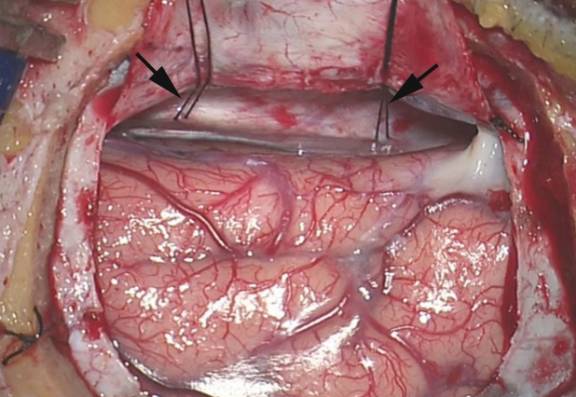

图10. 大脑镰缝线牵拉上矢状窦,扩大纵裂入路空间。

图11. 利用显微外科技术解剖双侧扣带回间的裂隙,充分暴露。需要谨慎避免软膜损伤。注意勿将扣带回误认为胼胝体(黑色箭头)。此时胼周动脉清晰可辨(红色箭头)。注意扣带回间的解剖需充分,大脑半球可以一定程度地向下游离,创造空间。

图12. 两团棉球(白箭头示)塞入术区两侧,撑开扣带回间隙空间,可替代牵开器的作用。